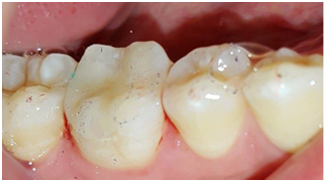

A 25years old male patient with unremarkable medical history, presented to the department of fixed prosthodontics with esthetic and functional demand. His chief complaint was to replace the defective amalgam restoration on the first right mandibular molar (Figure 1). A comprehensive clinical examination revealed good hygiene, a defective amalgam restoration on the first right mandibular molar, which caused a papilla inflammation between the 46 and the 47.

Figure 1 Defective amalgam restoration on the first right.